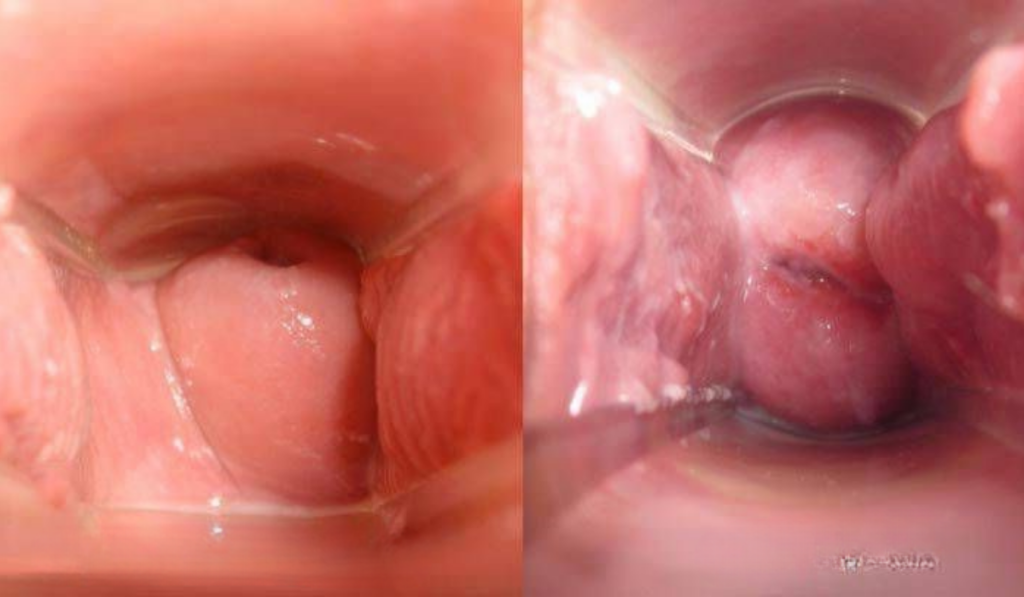

2. Hình ảnh ngứa do sùi mào gà

- Mô tả hình ảnh: Xuất hiện các nhú gai nhỏ, mềm, màu hồng tươi hoặc trùng với màu da.

- Dấu hiệu nhận diện: Ban đầu có thể ngứa nhẹ hoặc không đau. Theo thời gian, các nốt sùi liên kết thành mảng lớn có hình dạng như hoa súp lơ hoặc mào gà, dễ chảy máu khi va chạm.